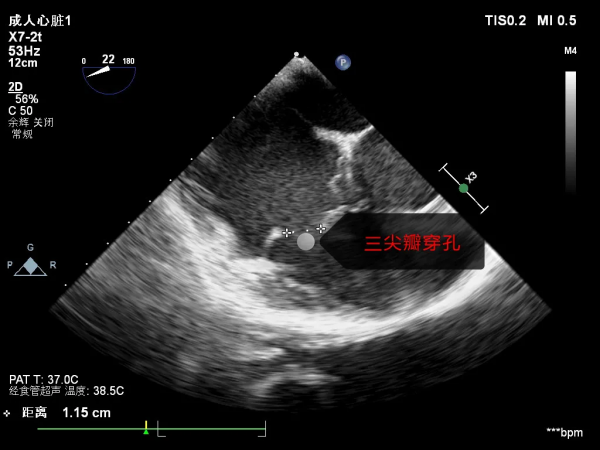

竇瘤在異常血流的衝擊下造成心臟內膜損傷感染,三尖瓣和主動脈瓣葉被細菌侵蝕、潰爛穿孔,瓣膜重度關閉不全,導致小趙出現心衰。

術中探查發現:主動脈竇瘤破裂入右房衝擊三尖瓣,主動脈瓣一個瓣葉穿孔,三尖瓣前葉巨大穿孔,二尖瓣上也見到少量細菌感染的贅生物。因主動脈瓣及三尖瓣毀損嚴重,手術團隊決定更換為人造機械瓣膜,並去除了二尖瓣贅生物,瓣膜大部分組織尚好,修復成功。